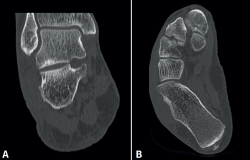

rpt.3702.fs2302004-figura6.png

Figura 6. Tomografía computarizada (TC) sin contraste realizada a las 4 semanas de la intervención quirúrgica. A: corte coronal de TC postoperatoria; B: corte axial de TC postoperatoria.